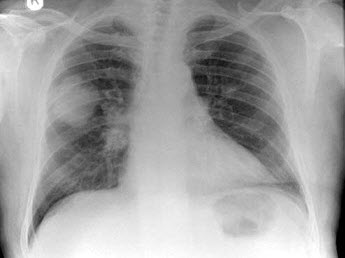

48、单项选择题

男,66岁,近1月来感胸闷,有时低热,胸片如图,最可能的诊断为()

A.化脓性胸膜炎

B.结核性胸膜炎

C.右下肺炎症

D.右下肺不张

E.右侧胸腔积液

点击查看答案